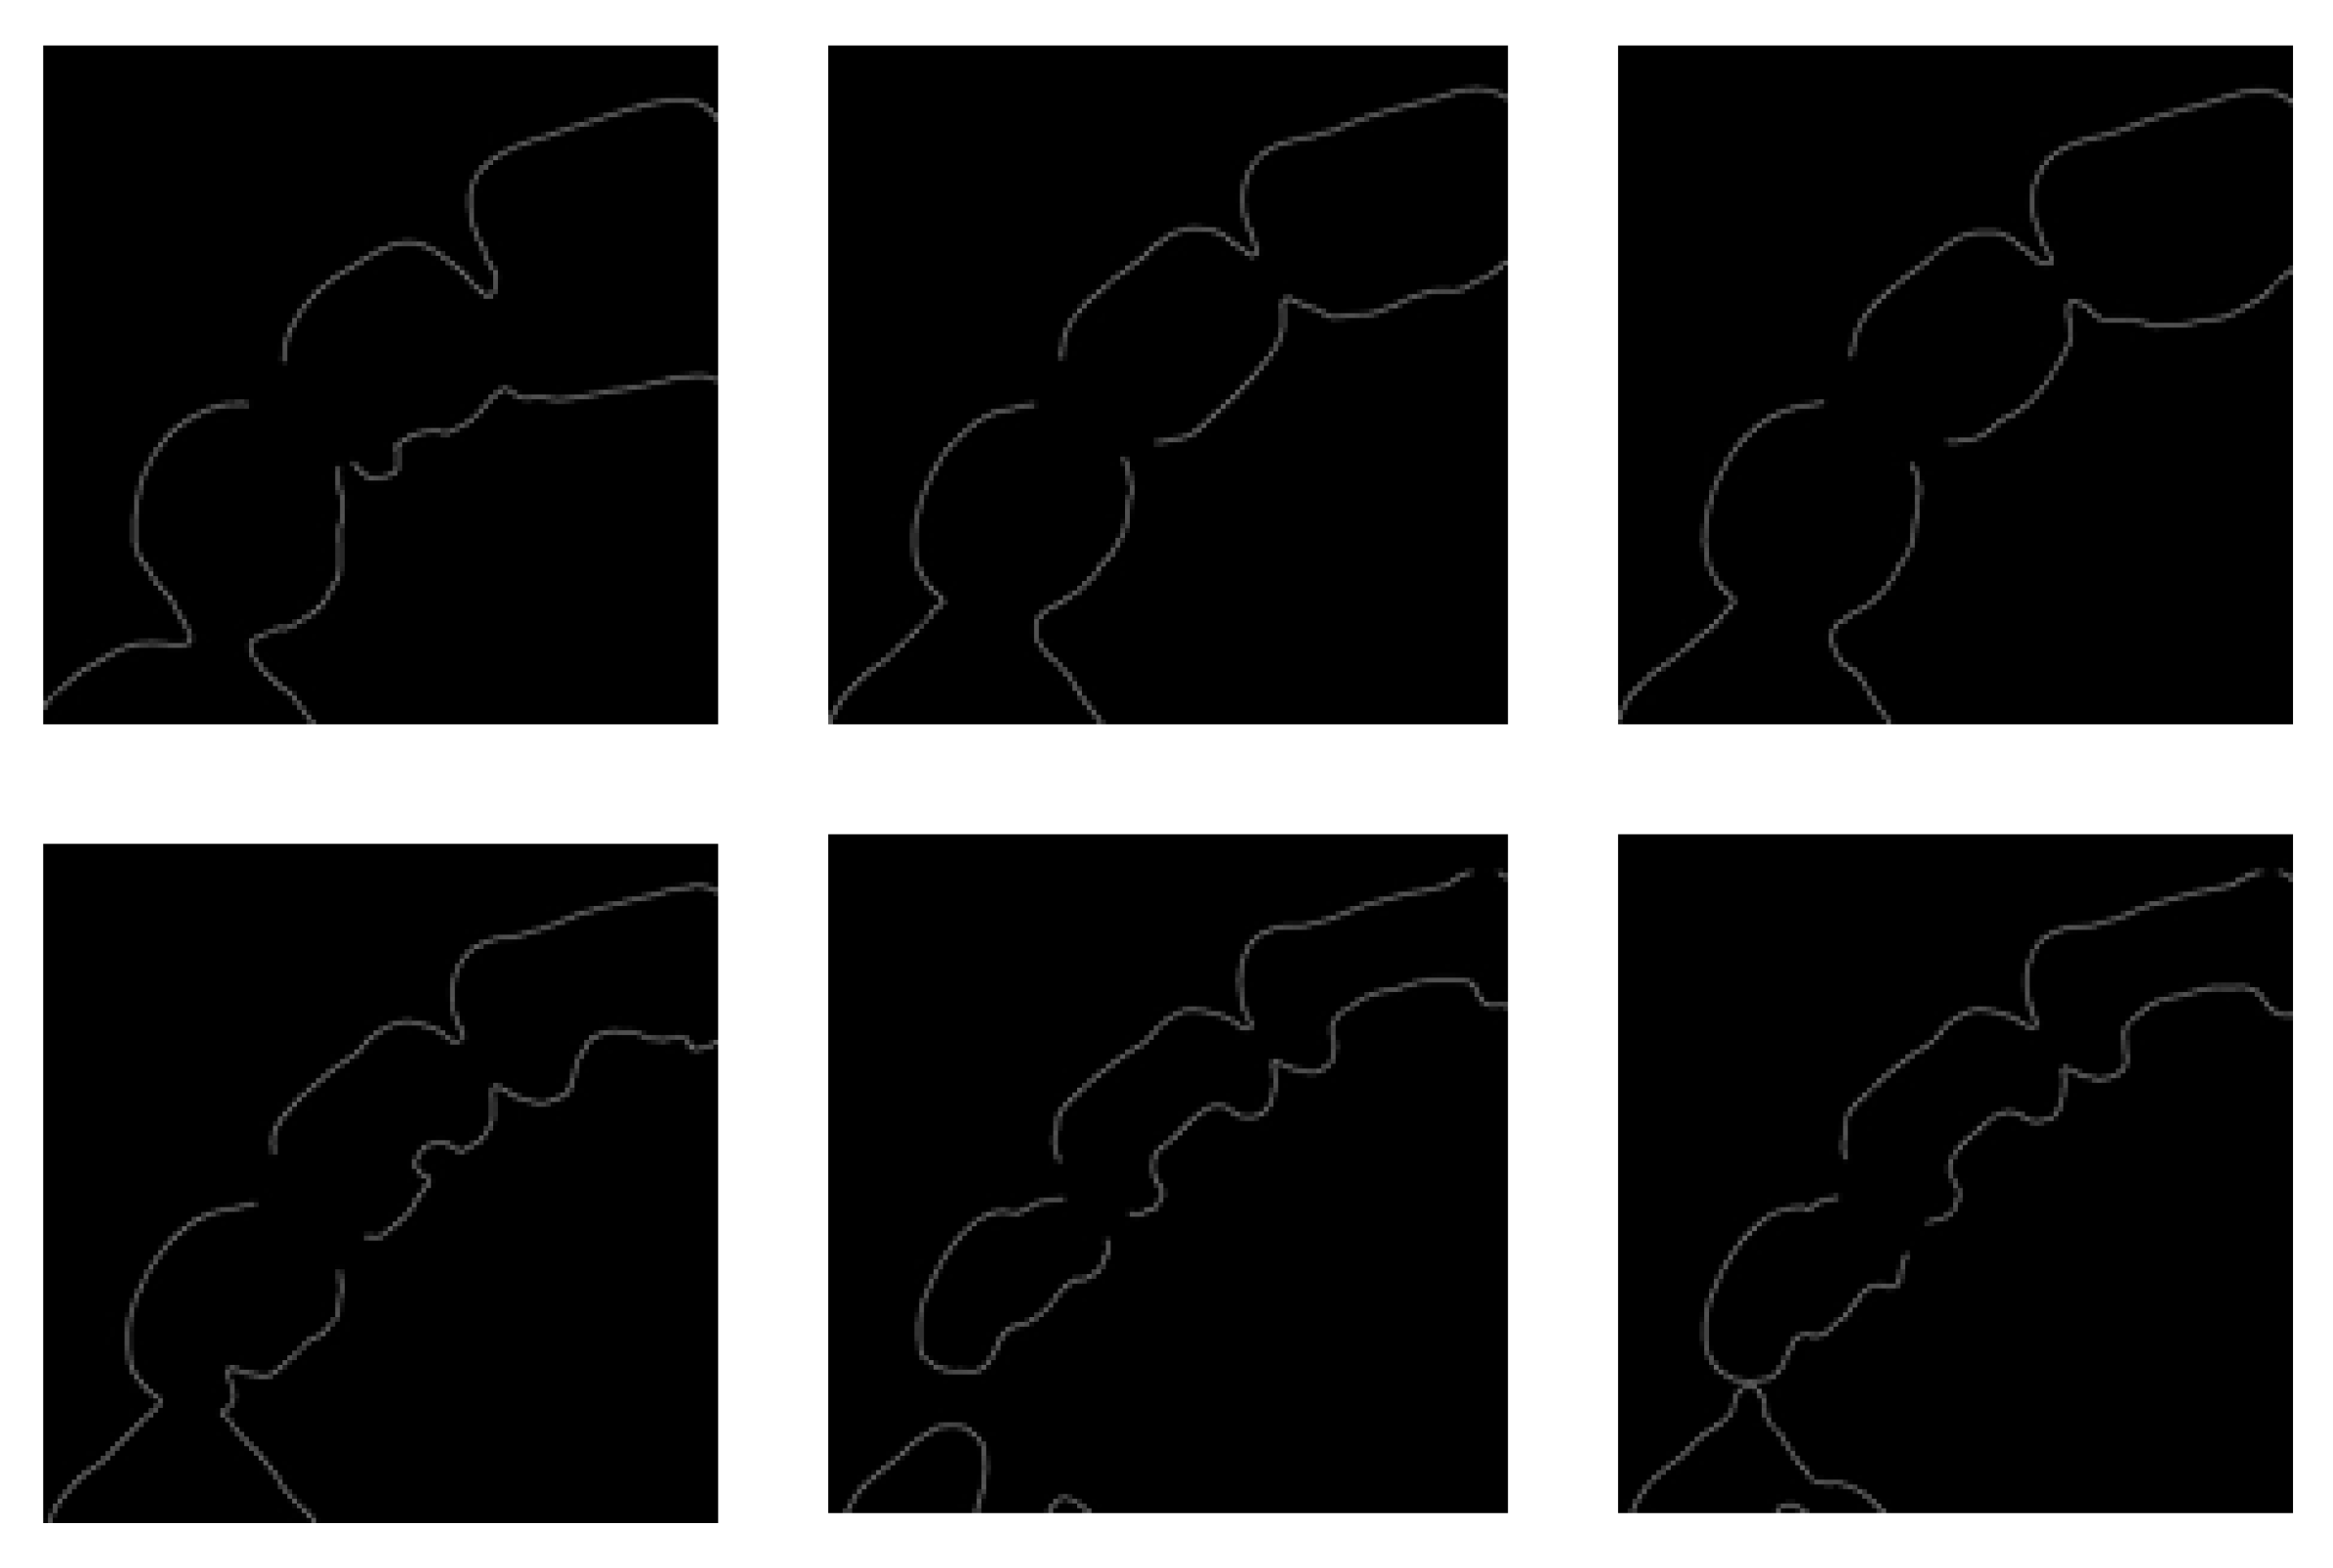

2.3.1. Data Preparation

2.3.2. Training Steps